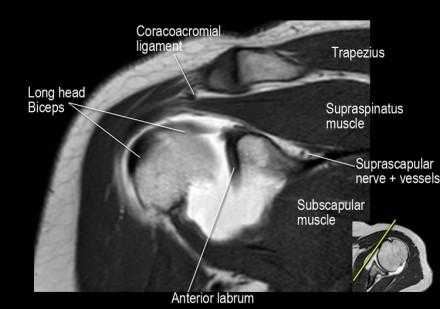

Нормальная корональная анатомия плечевого сустава и контрольный список

- обратите внимание на надлопаточный нерв и сосуды (suprascapular nerve and vessels)

- изучите верхний комплекс двуглавой мышцы и суставной губы, поищите подгубный карман илм SLAP-повреждение

- изучите область прикрепления нижней плече-лопаточной связки. Изучите нижний комплекс суставной губы и связок. Поищите HAGL-повреждение (humeral avulsion of the glenohumeral ligament).